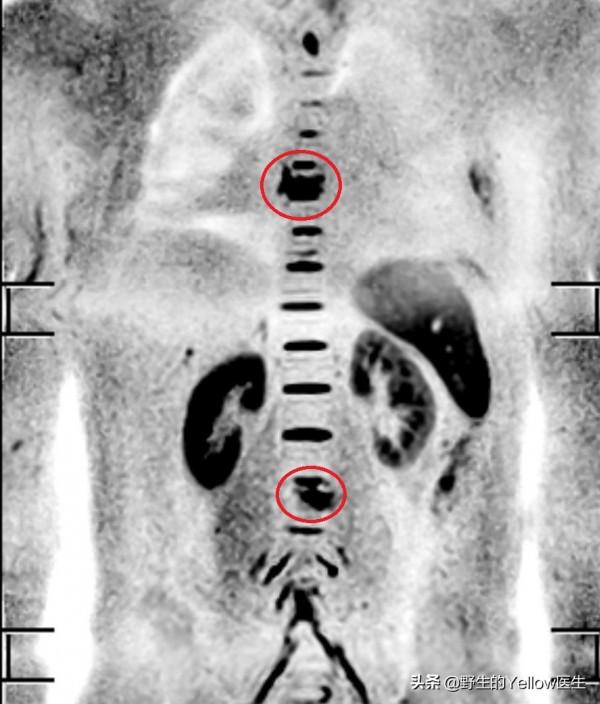

因為是醫院的同事,我們多留了個心眼。發現他的胸椎跟右肺門MRI訊號不對勁。

建議他做胸部CT。最終診斷為右肺中央型肺癌,伴肺門淋巴結、胸椎轉移。

而他的背痛,是由於胸椎轉移引起的。